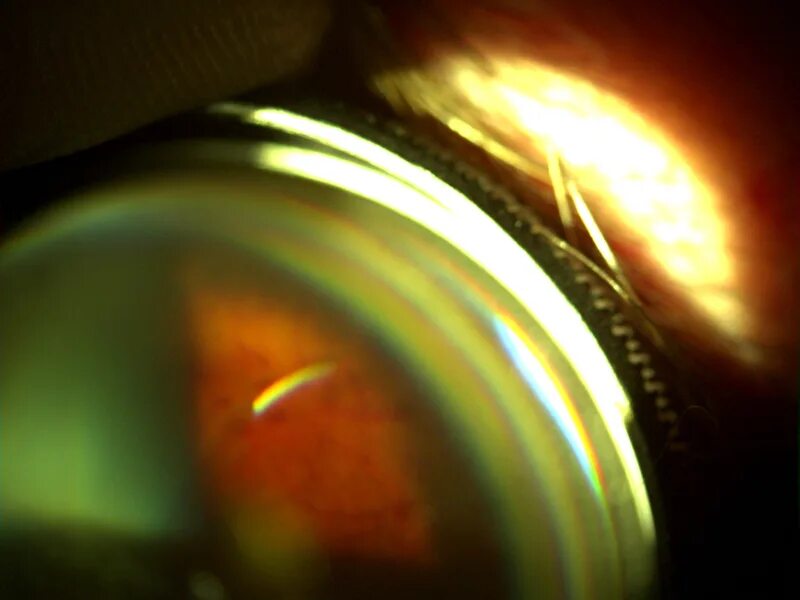

Озурдекс имплантат для интравитреального